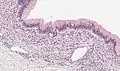

Micrograph showing a mucinous cystadenoma of the ovary. H&E stain. | |

Mucinous cystadenoma is a benign cystic tumor lined by a mucinous epithelium. It is a type of cystic adenoma (cystadenoma).